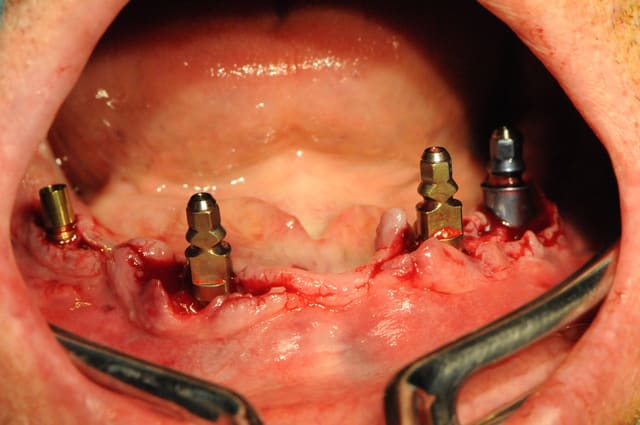

les photos...

pourquoi 4 implants et comment vont fonctionner les cavaliers ?

4 parce que le patient ne peut pas en mettre plus pour l'instant et que cela me permettra de passer plus tard en fixe.

quant à la position des cavaliers, c'est vrai que trois c'est trop, deux latéraux c'est pas super , et, un seul central c'est presque du sur traitement pour en arriver à ça.

mais encore une fois le but est de passer dans les deux ans à du fixe dés que ses finances le lui permettront.

je vais certainement faire une barre simple pour question de coût, bien que la fraisée avec une prothèse type stellite me plairait d'avantage.